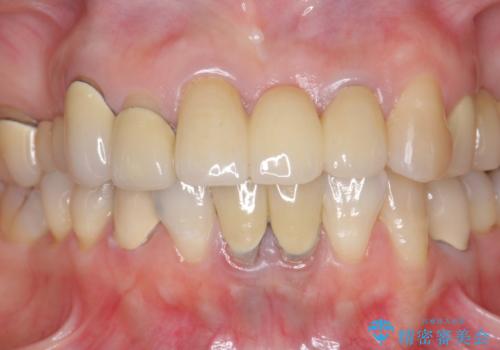

前歯ブリッジのやりかえ

- 前歯の審美障害、見た目の改善を希望され来院されました。

歯肉縁下カリエスも認められるため、挺出を行いセラミックブリッジを審美的に新製します。

- 47万円(仮歯×3・ファイバーコア×2・ジルコニアクラウン×3 歯の挺出)費用は治療当時の料金となります

虫歯が深くなった場合、挺出や歯周外科を行い歯周組織の状態を改善することでより安定した状態で予知性の高いセラミックブリッジを製作することが可能となります。